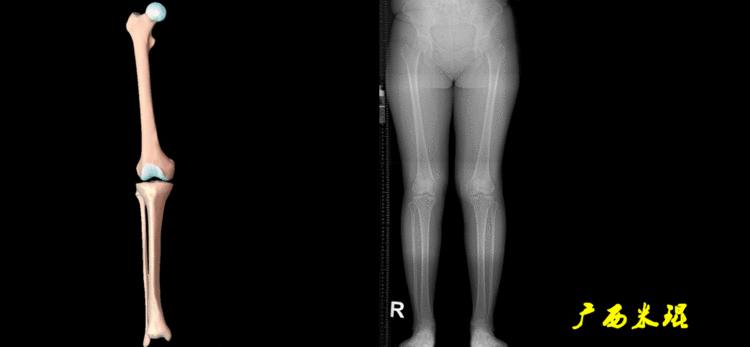

下肢力线及相关角度测量的前提是必须拍摄标准的站立位也就是负重位的下肢全长片。目前这样的照片都是放射科的技师在电脑上拼接出来的,大部分医院的DR都能够做到这一点。

无论如何,拍摄出来的下肢全长片必须包含髋关节中心、膝关节中心及踝关节中心,否则对临床是无用的。有了一张下肢的全长照片,我们需要确定下肢关节的中心点,通过中心点画出下肢的各种轴线,然后利用轴线与关节线的相交得出各种所需要的角度。

2、画出下肢的轴线确定髋关节、膝关节、踝关节的中心点后,我们才能了解下肢的几个轴线。(1)解剖轴股骨和胫骨的骨干中线为解剖轴,股骨解剖轴和胫骨解剖轴的夹角正常值为174°±1°。

(2)机械轴机械轴是连接近端和远端关节中心点的直线。

机械轴要分前后位及侧位,站立前后位(也就是冠状面)股骨头中心与踝关节中心的连线通过膝关节中心,这是下肢的机械轴线,也就是下肢力线,常说Mikulicz线。冠状面的力线评估在临床工作中最常用、最基础、最重要。